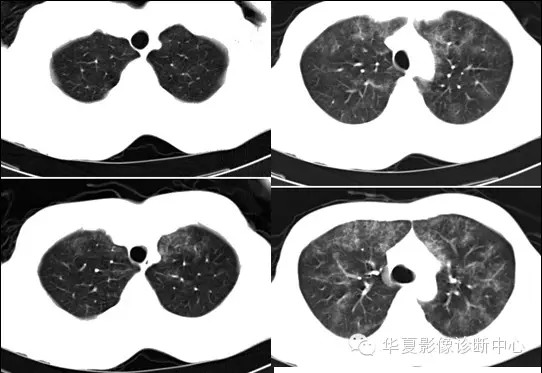

两肺野弥漫性分布的斑点及斑片状阴影,呈“暴风雪”样,病变以两中下肺野为多,部分小叶间隔增厚,心脏大小正常。纵隔窗显示右侧胸腔后下部少量积液。。